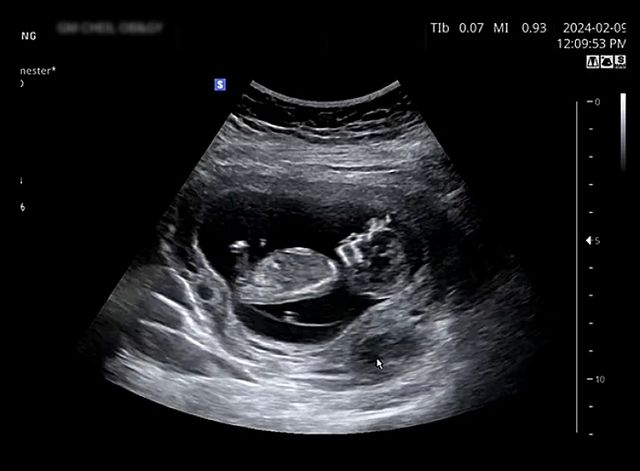

이성진 부부의 2세 모습이 담긴 초음파 영상 / 이성진 인스타그램

또 다른 영상에는 엄마 배 속에서 건강하게 자라고 있는 2세의 초음파가 담겨 눈길을 끌었다.